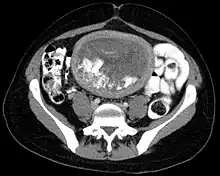

Hydatidiform mole on CT, sagittal view

Hydatidiform mole on CT, axial view

The diagnosis is strongly suggested by ultrasound (sonogram), but definitive diagnosis requires histopathological examination. On ultrasound, the mole resembles a bunch of grapes ("cluster of grapes" or "honeycombed uterus" or "snow-storm").[14] There is increased trophoblast proliferation and enlarging of the chorionic villi, and angiogenesis in the trophoblasts is impaired.[15]